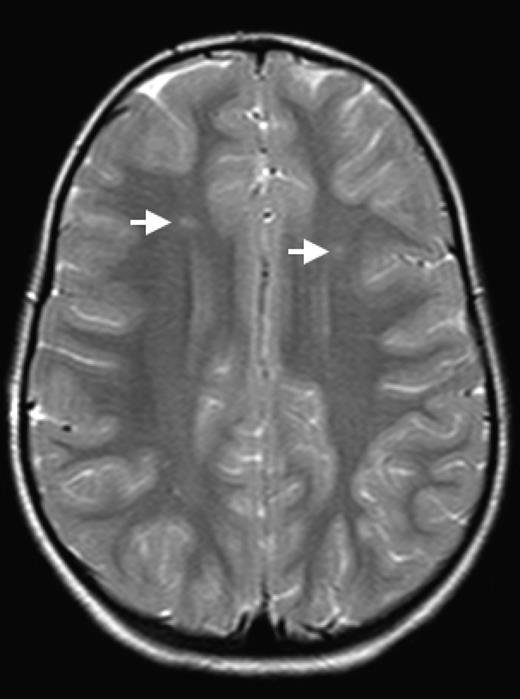

The brain is at constant threat of ischemic injury in sickle cell disease (SCD). The risk of overt stroke for children with SCD is more than 200 times higher than that for the general population, and this burden of overt stroke continues well into adulthood. An even more common form of neurologic injury in SCD is silent cerebral infarction (SCI), which has a prevalence of up to 40%. SCI refers to generally small, permanent brain lesions that are not associated with obvious focal neurologic signs (Figure 1). The term SCI is a misnomer because these strokes, even though they do not produce focal or localizing signs on neurologic examination, are often not “silent.” SCI is a morbid condition associated with neurocognitive impairment, poor academic performance, neurologic soft signs, and increased risk for subsequent overt stroke. Covert cerebral infarction may be a better descriptor, but SCI is the accepted term.

SCI. Two typical SCI lesions (arrows) are shown in the frontal and deep white matter in a T2-weighted magnetic resonance image of the brain in a child with sickle cell anemia.